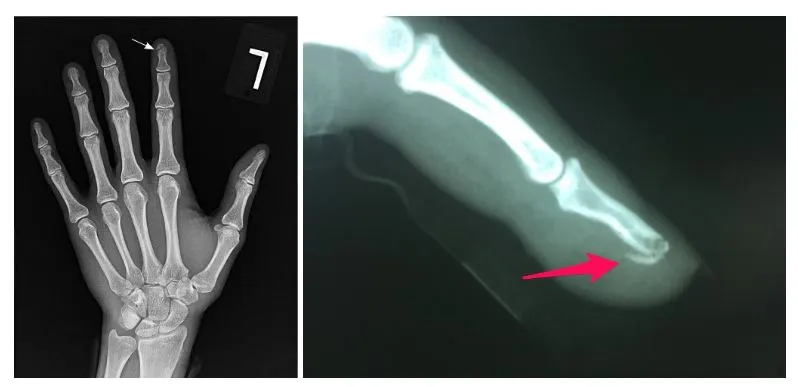

캡처.JPG < 손가락 끝이 골절이 된 엑스레이 사진 >

위의 사진처럼 치료를 하고 나서도 뼈조각이 계속 떨어져 있는 경우가 있습니다. 저도 중학교 때 농구를 하다 다친 손가락 마디 끝에도 조각이 떨어져 있습니다. 진짜 오래 전 기억이지만 그 당시 선생님이 이 조각은 붙일 수 없고 그렇다고 살아가는데 지장이 있는 것이 아니다라고 말씀하신 것이 기억이 납니다.